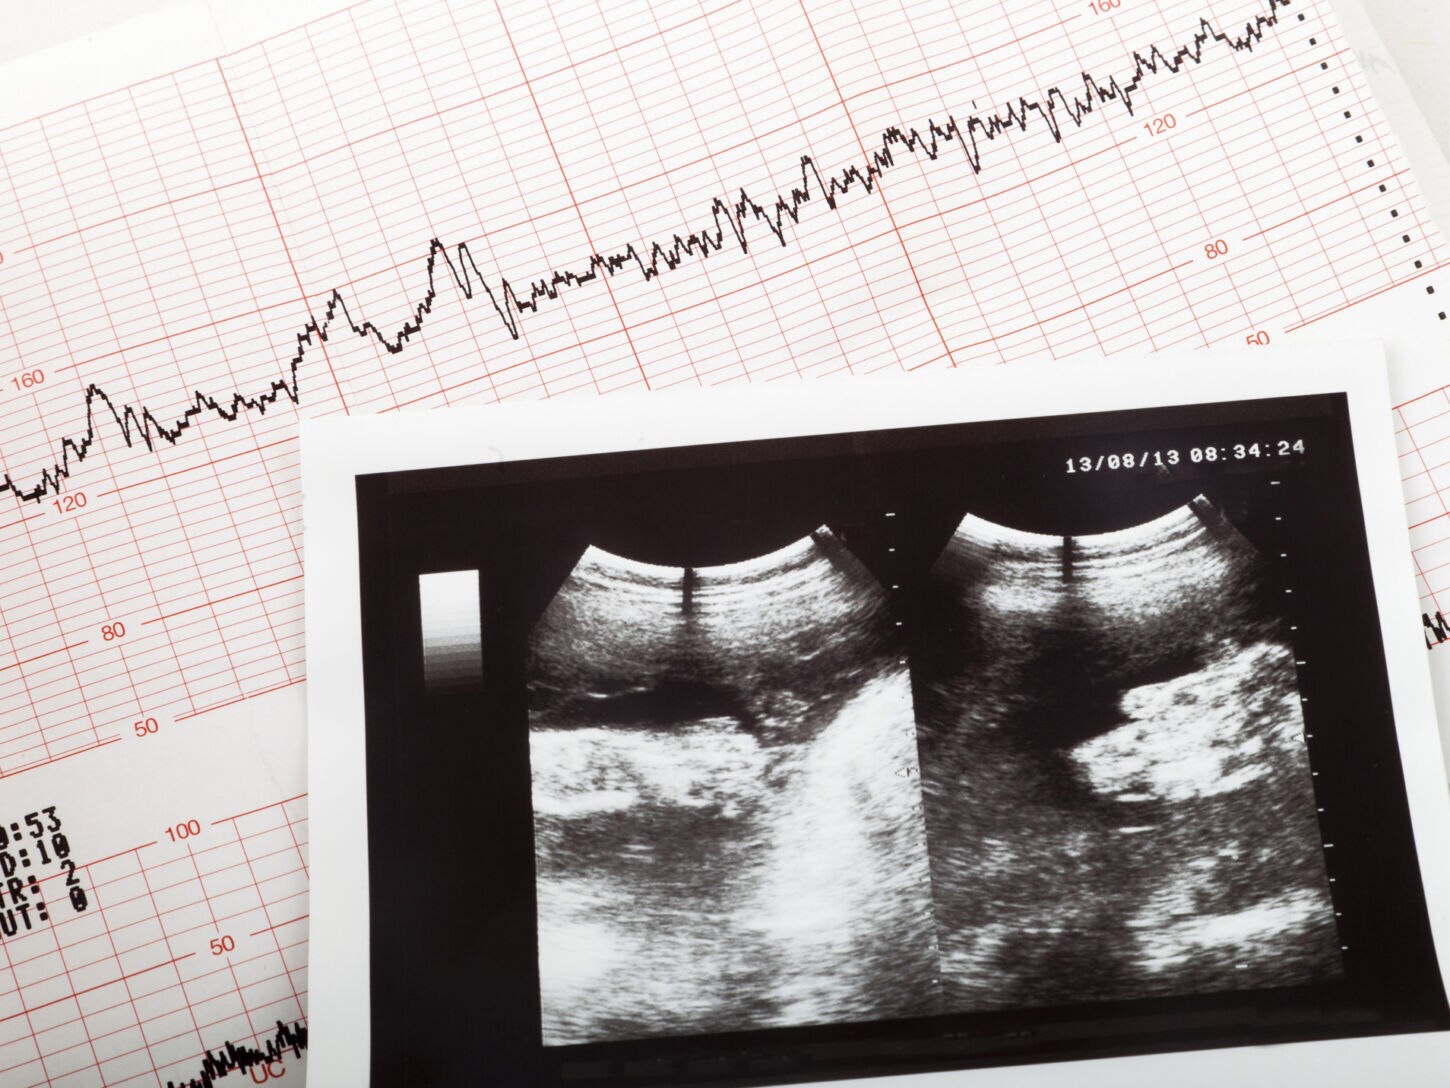

El proyecto de ley conocida como «Ley del latido», busca que sea obligatorio realizar un ultrasonido a toda mujer que solicite un aborto.

El ultrasonido debe ser “realizado por personal capacitado e idóneo de conformidad con las prácticas médicas estándares, a los efectos de determinar la detección de latidos fetales”.

Si este estudio detecta latidos fetales del bebé no nacido entonces este no podrá ser eliminado.

El primer latido de un bebé se produce a los 16 días de la concepción. https://t.me/QAnons_Espana

Sin embargo, en general es a partir de las 6 ½ -7 semanas en que un latido del corazón puede ser detectado con la tecnología que existe en cualquier centro de salud.